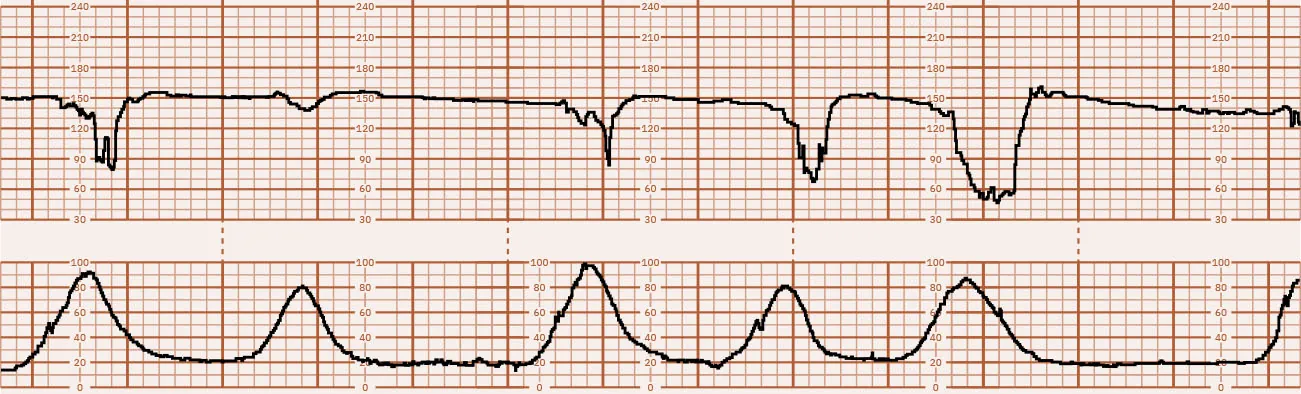

Category I tracings are considered normal and do not require further actions by the nurse other than routine nursing care for the antepartum or laboring patient. Figure 16.26 shows a Category I tracing. Category II tracing characteristics do not meet the criteria of either Category I or III. Nursing care requires continued surveillance with consideration of clinical circumstances and reevaluation and notification of the health-care provider. Figure 16.27 shows a Category II tracing. Category III tracings are always considered abnormal and require the nurse to contact the health-care provider with a report of the FHR abnormalities. Nursing interventions aimed at resolving the cause of the abnormality are discussed in 16.5 Intrauterine Resuscitation in this chapter. If interventions do not resolve the abnormality, the birth must be expedited, most commonly via cesarean section (ACOG, 2009). Figure 16.28 shows a Category III tracing.

Fetal heart rate reading showing absent variability with repeat variable decelerations with uterine contractions every two to three minutes.

Figure 16.28 Category III Tracing This fetal heart rate tracing shows absent variability with repeat variable decelerations with uterine contractions every 2 to 3 minutes. (attribution: Copyright Rice University, OpenStax, under CC BY 4.0 license)